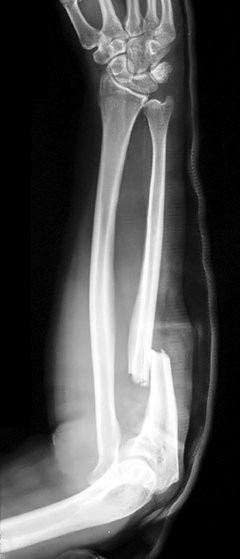

Osteoporosis paling sering terjadi pada tulang pinggul, tulang belakang, dan pergelangan tangan. Tulang terdiri dari sel-sel yang rutin diganti. Penyakit osteoporosis terjadi ketika proses penyusunan sel tulang baru tidak seimbang dengan sel tulang lama yang hilang. Osteoporosis dapat terjadi pada pria dan wanita dari seluruh ras dan etnis.

• Patah tulang secara tiba-tiba tanpa riwayat cedera.

• Sering mengalami patah atau keretakan tulang.

• Rontgen, CT scan atau MRI untuk melihat pencitraan area tulang atau jaringan-jaringan di sekitarnya.

Komplikasi dari osteoporosis yang cukup serius adalah patah tulang, terutama pada bagian tulang belakang dan tulang pinggul. Patah tulang pinggul paling sering disebabkan karena insiden terjatuh. Patah tulang bisa menyebabkan disabilitas permanen serta kematian dalam satu tahun pertama setelah cedera.

Sementara itu, patah tulang belakang dapat terjadi tanpa adanya insiden terjatuh. Tulang yang menyusun tulang belakang dapat melemah dengan sendirinya akibat massa jenis tulang yang menurun drastis dan merubah postur tubuh.